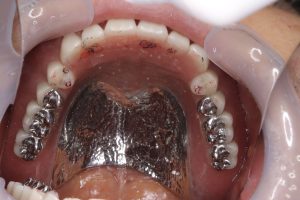

本日のケースは、以前オルタードキャスト印象した方(先月に、ブログアップ)、新大久保歯科に50年間通院されてる大切な患者さんであります

前歯でも噛みたいのリクエストに応えて舌面テーブルを付与

顎堤条件も良く、根面板もあり

深いポストダム深さは3ミリ近く削り込みし、サイドビーディングもしてます

結果、水を含んでも陰圧解除出来ず、また私の指力でも全く外れず、更には厚みある止血ガーゼ前噛みでも外れない、最強の入れ歯に仕上がりました!

噛み合わせも、画像通り安定

全くブレずに、good!